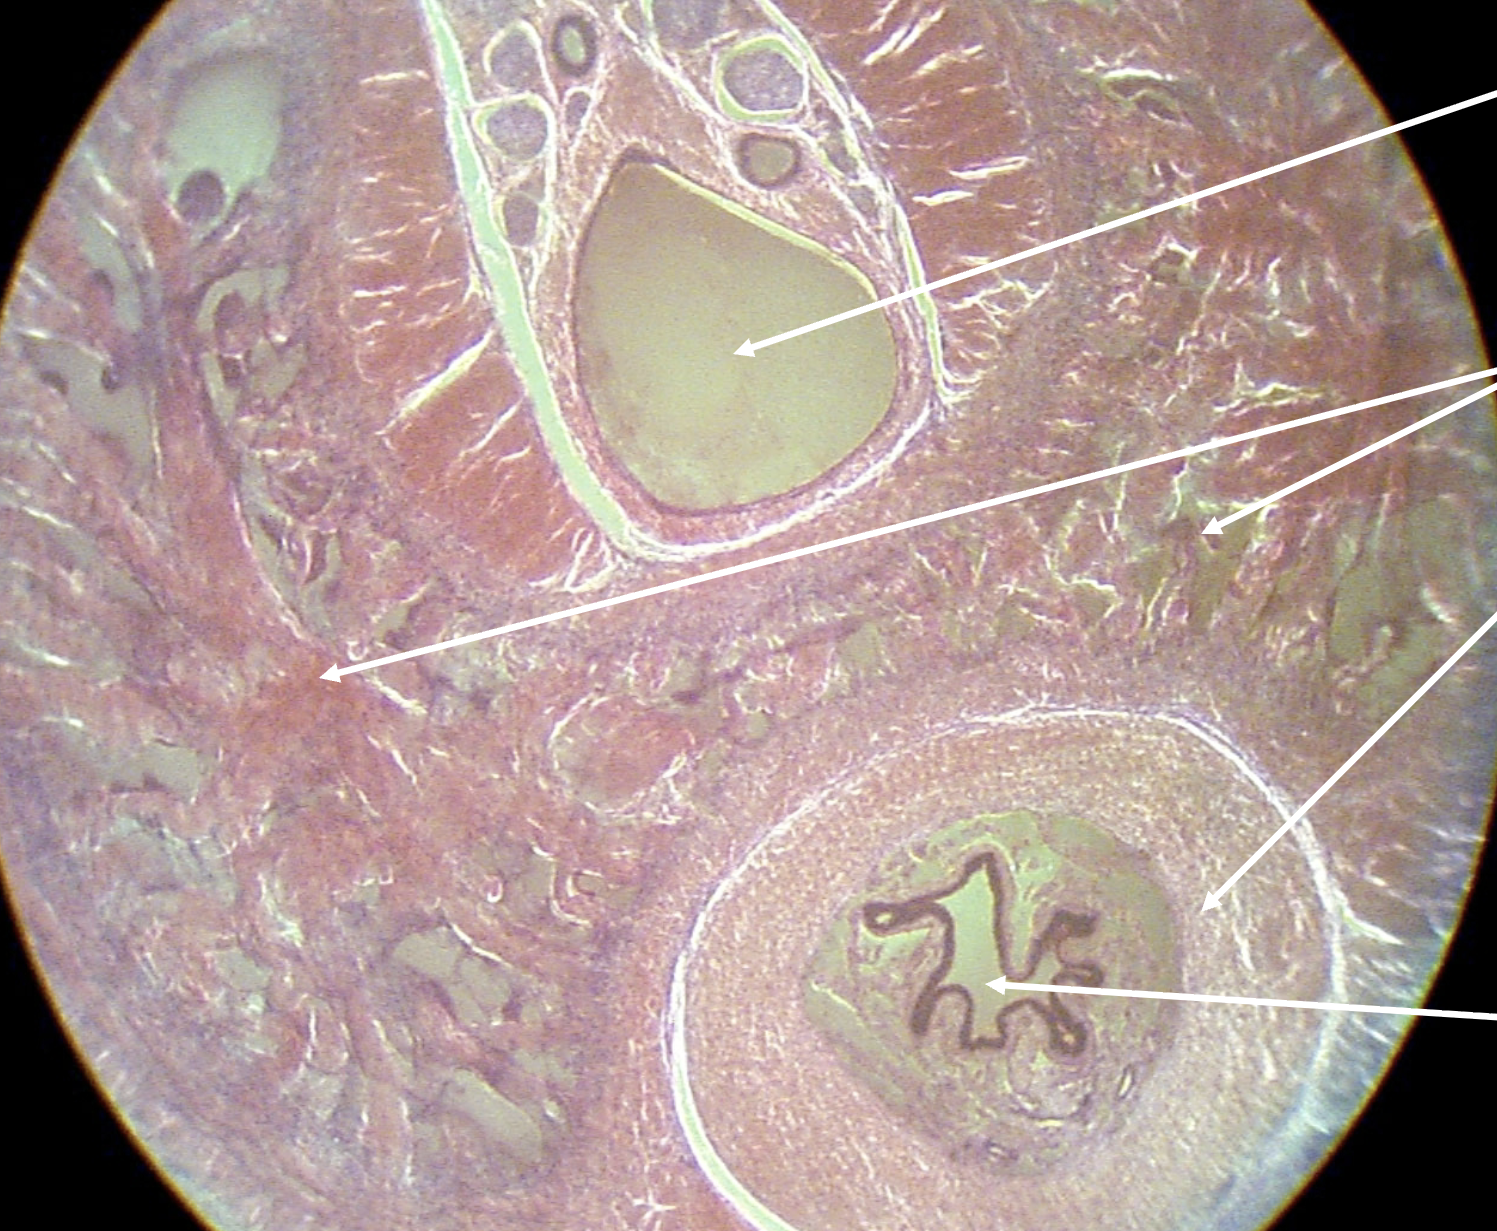

What structure is depicted within the micrographs?

*Hint: This is a paired accessory sex gland that has many interconnecting folds providing a “fishnet” appearance.

Vesicular gland

What structure is depicted within the micrograph?

Prostate gland (corpus)

Which structures are being indicated by the above arrows?

Finger-like evaginations of the mucosa

Which structures are being indicated by the lower arrow?

Lamellar concretions